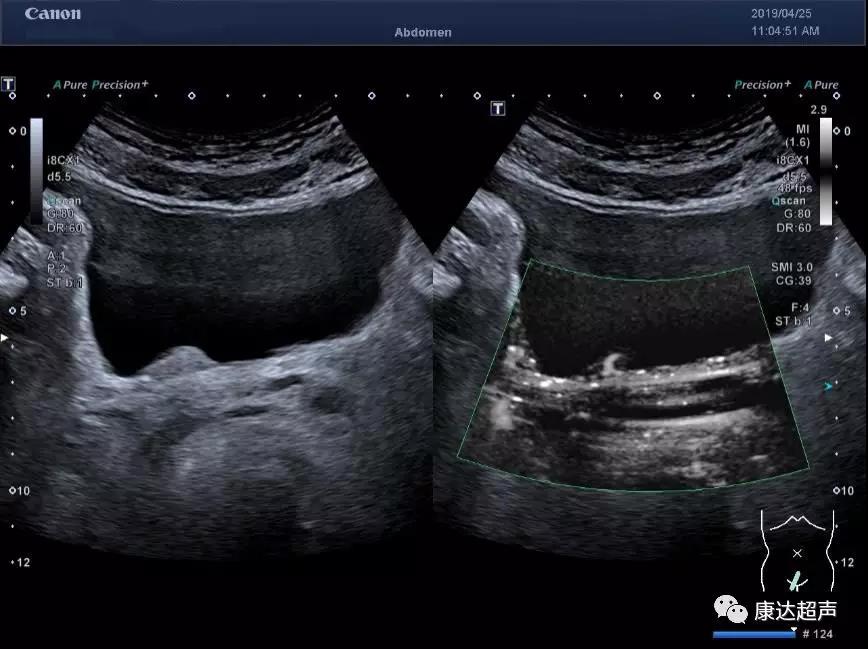

二维超声发现一个膀胱占位

彩色多普勒以及能量图显示,其内未见明显血流信息

应用佳能的超微血流成像技术(SMI)可以清晰显示其内血流情况以及血流动力学信息。